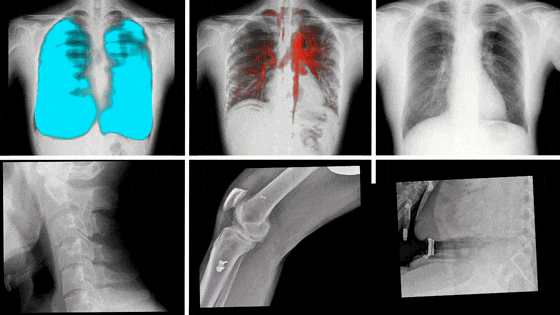

動(dòng)態(tài)DR,是近些年來迅速發(fā)展的影像技術(shù),其具備動(dòng)態(tài)/靜態(tài)兩種模式,這意味著除了能像傳統(tǒng)靜態(tài)DR進(jìn)行普通的X片拍攝外,還能通過高幀率、多角度的采集技術(shù),捕捉拍攝部位的實(shí)時(shí)動(dòng)態(tài),將短時(shí)間內(nèi)拍攝的數(shù)百張圖像合成為一個(gè)動(dòng)態(tài)視頻。

動(dòng)態(tài)DR影像

隨著科學(xué)技術(shù)的不斷發(fā)展,動(dòng)態(tài)DR在未來還將擁有更多的發(fā)展空間,在更多領(lǐng)域得到應(yīng)用,如兒科、骨科、呼吸科等,為更多患者提供高質(zhì)量的醫(yī)療服務(wù)。